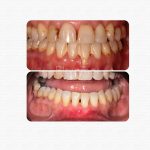

Casos reales de antes y después

Cada sonrisa tiene una historia. En Clínica Dental Blaumar te mostramos casos reales de pacientes que confiaron en nosotros para mejorar su salud y su estética dental. Antes y después, procesos y resultados explicados con claridad, para que veas cómo trabajamos: con planificación, precisión y un trato cercano de principio a fin.